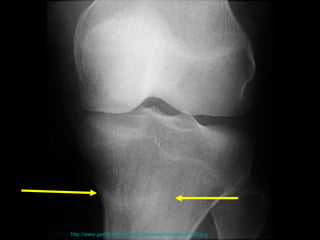

壓力性骨折 Stress Fracture 疲勞骨折 Fatigue fracture   骨質不良性骨折 Insufficiency fracture http://www.emedicine.com/radio/topic783.htm

the failure of the skeleton to withstand submaximal forces over time.  the failure of the skeleton to withstand submaximal forces over time.  http://www.mypacs.net/repos/mpv3_repo/viz/full/17093/854689.jpg